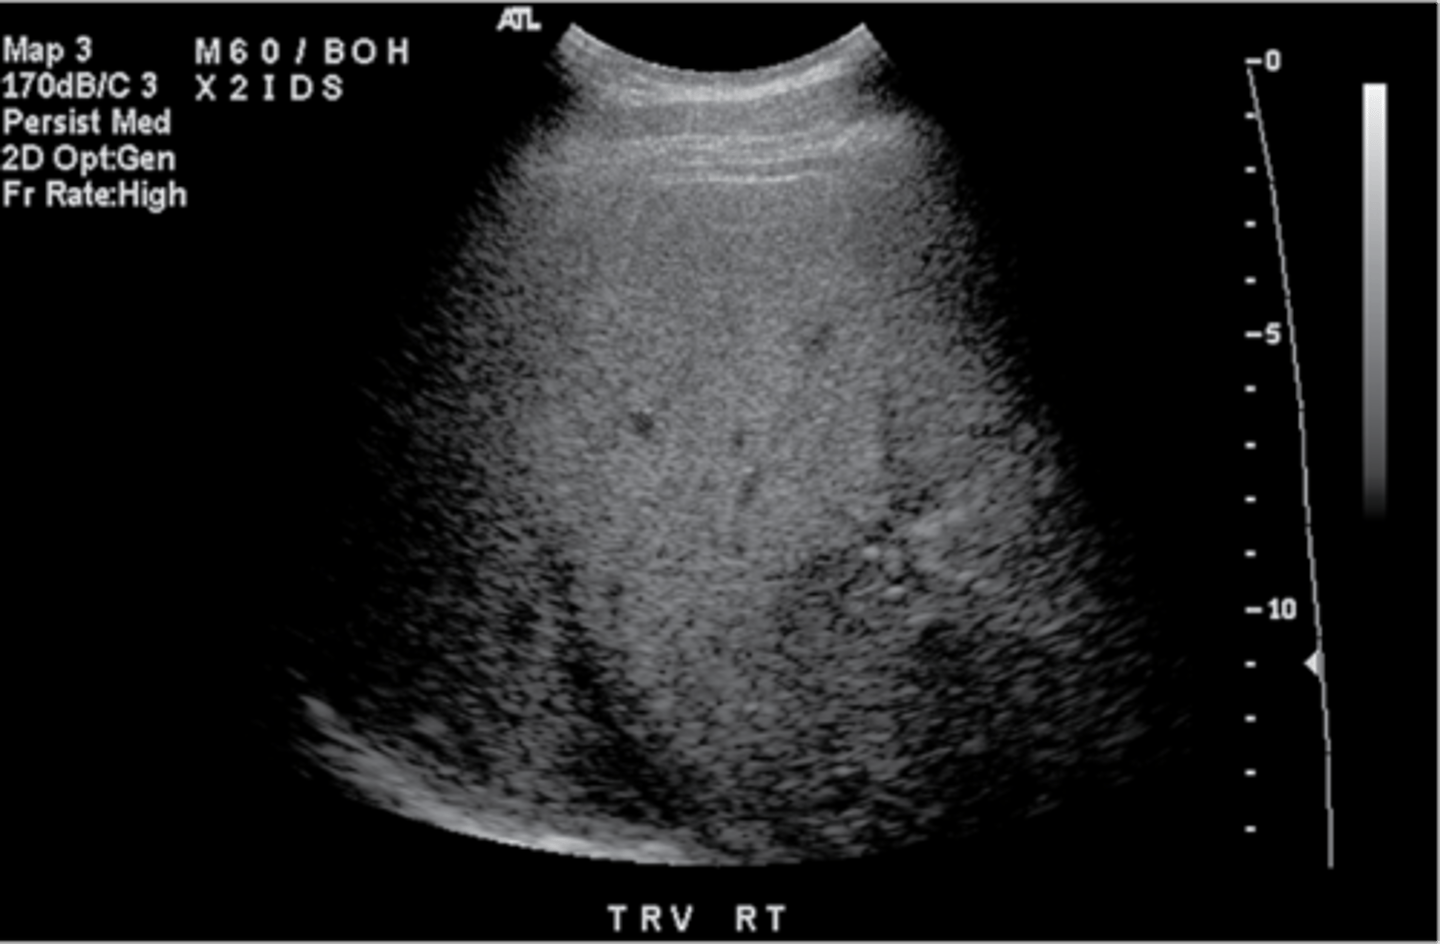

Normal

fatty liver (hyperechoic=too bright)

Hepatitis (hypoechoic=starry skies)

Inhomogeneous (normally a tumor)